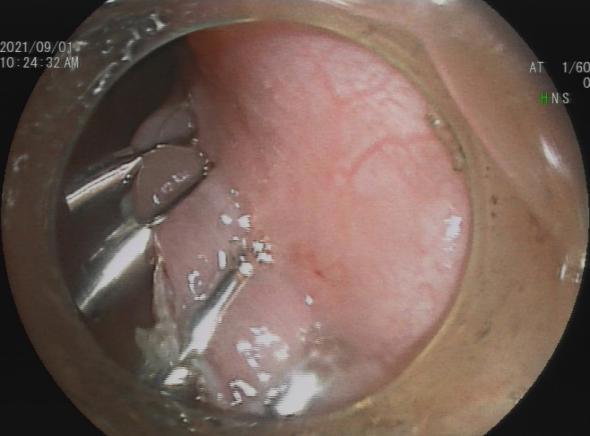

三、早期消化道肿瘤ESD技术

内镜下粘膜剥离术(ESD),具有超级微创、安全性高、住院时间短及费用低等优势。

直肠巨大绒毛状腺瘤 内镜下粘膜剥离过程

粘膜剥离术后创面 剥离的巨大腺瘤